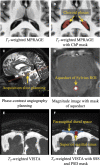

One of the pathological hallmarks of Alzheimer's and related diseases is the increased accumulation of protein amyloid-β in the brain parenchyma. As such, recent studies have focused on characterizing protein and related clearance pathways involving perivascular flow of neurofluids, but human studies of these pathways are limited owing to limited methods for evaluating neurofluid circulation non-invasively in vivo. Here, we utilize non-invasive MRI methods to explore surrogate measures of CSF production, bulk flow and egress in the context of independent PET measures of amyloid-β accumulation in older adults. Participants (N = 23) were scanned at 3.0 T with 3D T2-weighted turbo spin echo, 2D perfusion-weighted pseudo-continuous arterial spin labelling and phase-contrast angiography to quantify parasagittal dural space volume, choroid plexus perfusion and net CSF flow through the aqueduct of Sylvius, respectively. All participants also underwent dynamic PET imaging with amyloid-β tracer 11C-Pittsburgh Compound B to quantify global cerebral amyloid-β accumulation. Spearman's correlation analyses revealed a significant relationship between global amyloid-β accumulation and parasagittal dural space volume (rho = 0.529, P = 0.010), specifically in the frontal (rho = 0.527, P = 0.010) and parietal (rho = 0.616, P = 0.002) subsegments. No relationships were observed between amyloid-β and choroid plexus perfusion nor net CSF flow. Findings suggest that parasagittal dural space hypertrophy, and its possible role in CSF-mediated clearance, may be closely related to global amyloid-β accumulation. These findings are discussed in the context of our growing understanding of the physiological mechanisms of amyloid-β aggregation and clearance via neurofluids.